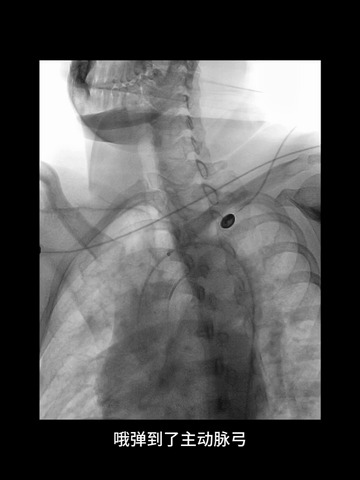

右股动脉穿刺置入8F短鞘,125cm长度5F多功能管塑成西蒙管头端形状,与6F长鞘(Cook,90cm)组成同轴,导丝导引下,5F管进入左锁骨下动脉,而后成其头端成西蒙管形,进入弓内。

西蒙管形头端超选入无名动脉,回拉导管时,习惯性进入右锁骨下动脉,间断冒烟下退回无名动脉,在旋转导管调整头端方向时,管头弹回弓内。

西蒙形管后续超选过程中,导管头还是习惯性进入左锁骨下动脉,调整导管头方向过程中,头端易弹回弓内。

耐心冒烟下,调整导管头在无名动脉内指向左侧,同时回拉导管,进入右CCA,后上高导丝,长鞘沿5F管顺利进入右CCA,后在导管导丝导引下,长鞘头端上高到右C1远端,建立可靠的治疗通路。